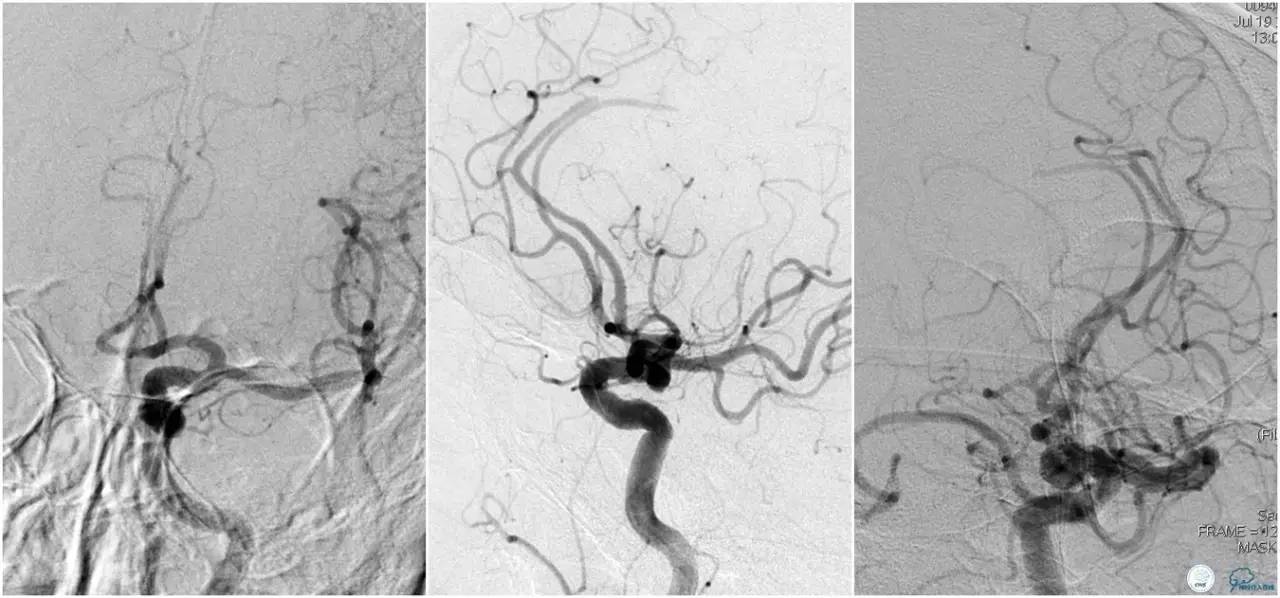

12:35穿刺成功,TOT 185min。3型主动脉弓,右侧颈内动脉起始部狭窄70%,右侧大脑前动脉A1段未显影。

双侧大脑前动脉A4段闭塞,右侧大脑前动脉由左侧大脑前动脉经前交通动脉代偿供血。

6F Envoy置于颈内动脉C3段,选用Solitaire-FR 4*20mm支架释放于右侧大脑前动脉,完全覆盖血栓。

6F Envoy置于左侧颈内动脉C3段,选用Solitaire-FR 4*20mm支架释放于右侧大脑前动脉取栓1次,血流达TICI 2b。

Solitaire-FR 4*20mm支架释放于左侧大脑前动脉取栓1次,取出少许血栓重复造影左侧大脑前动脉胼周动脉开口后,右侧大脑前动脉A2段以远未显影,考虑栓子逃逸。